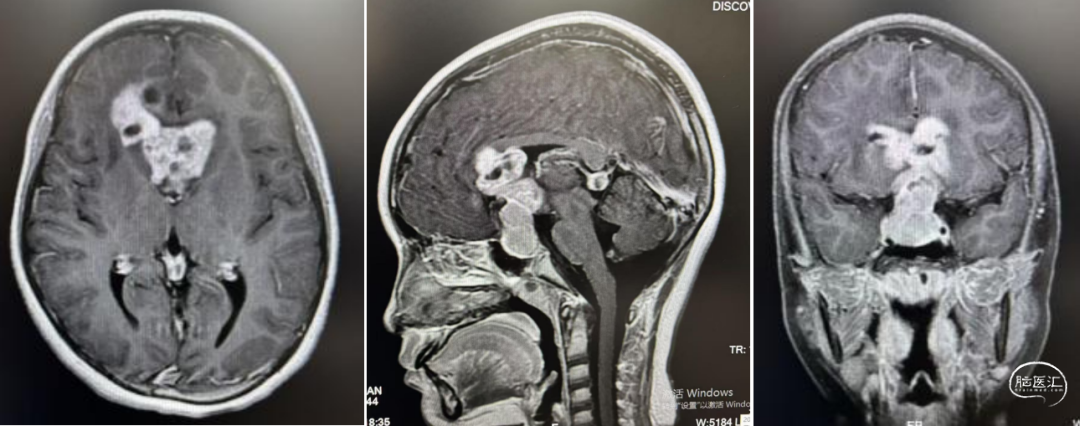

头部CT显示:鞍区-鞍上区-双侧额叶-胼胝体前份可见一不规则形囊实性肿块,实性部分密度稍高,平扫CT值约39HU,冠状位最大层面约55mm×36mm,平扫CT值约39-15HU,周围脑实质可见片状低密度水肿密度,双恻脑室前角受压,中线结构无移。

头部MRI显示:鞍区-鞍上区-双侧额叶-胼胝体前份可见一不规则形等-长T1等-长T2信号囊实性团块灶,FLAIR呈等-稍高信号,DWI示实性部分稍高信号,相应ADC低值,增强扫描病灶实性部分明显强化;邻近脑实质见片状FLAIR高信号,双侧侧脑室前角受压,中线结构无移位,脑沟、脑裂未见明显增亮。松果体区见环形强优结节,直径约9mm。

经儿童脑肿瘤MDT讨论后,建议先化疗再放射治疗。1疗程后病变明显退缩,甲胎蛋白(AFP)、人绒毛膜促性腺激素(β-HCG)降至正常范围。结疗后复查,肿瘤完全消失,无复发。此后1年予以定期复查未见复发。

1疗程后评估